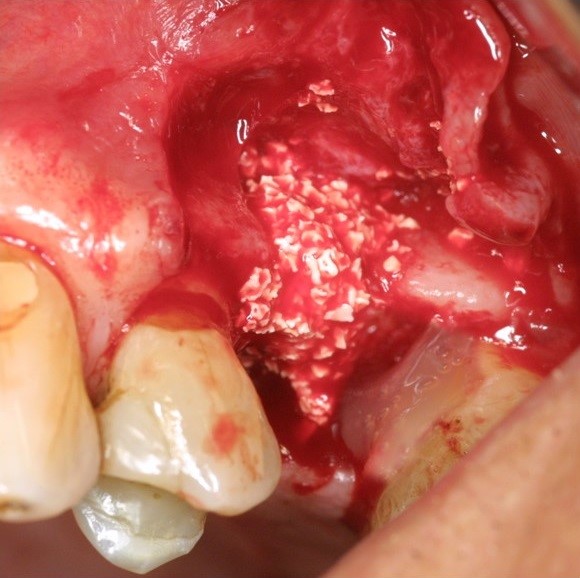

Intrabony defect treated using collprotect® membrane & cerabone® (1) - Cosgarea & Sculean

Pre-surgical probing reveals a deep intrabony defect on the distal aspect of the upper canine.